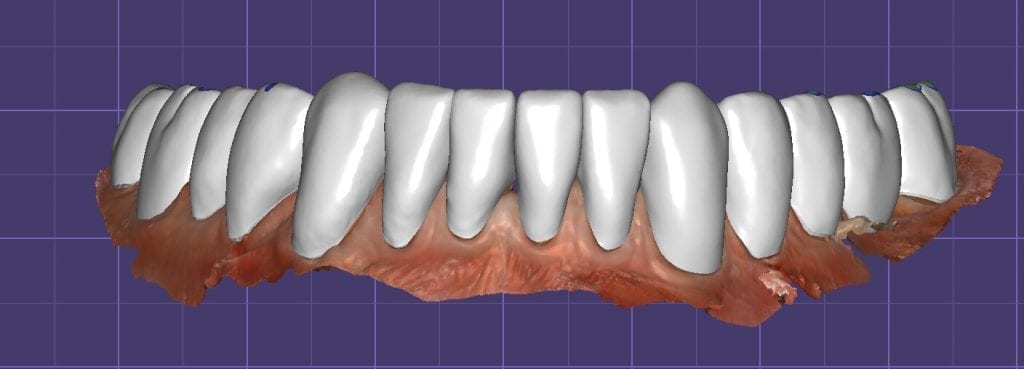

Once the appropriate library is chosen, the digital wax ups are performed. In the subsequent photos you can see the transparent overlay of the wax-ups to the original position of the existing dentition

Over the course of a few appointments, the vertical dimension was reduced and the temporaries were adjusted to the patient’s desires. The new upper and lower arch were captured with the Medit i500 and the jaws were related to each other.

This was then imported into exocad where the prepped arches from a few weeks prior were force matched to the new bite

After the upper jaw was related to the temps, the same was done with the lower arch. Great care was taken to make sure the arches were properly related to each other throughout the process